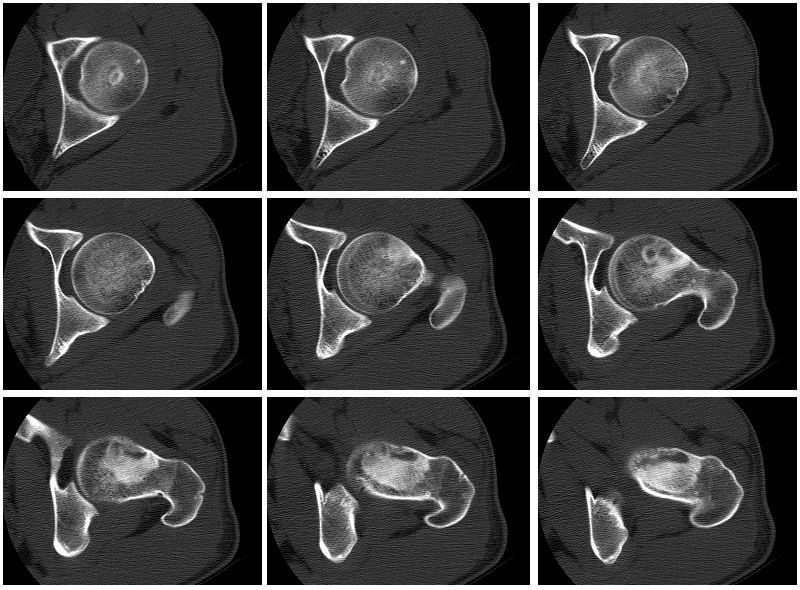

标题: CT27262:左股骨上段骨肿瘤 [打印本页]

标题: CT27262:左股骨上段骨肿瘤

男性,27岁,左髋部疼痛两三个月余,右侧髂骨因右侧股骨下端骨折,取骨植骨后改变

考虑左侧股骨颈及粗隆骨纤维异常增殖症。

磨玻璃样,男27岁考虑骨纤。